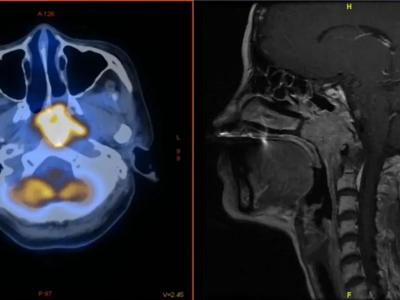

研究发现在接种中国SinoVac(科兴新冠疫

COVID-19疫苗接种对鼻咽癌疗法产生不利影响的担忧似乎是没有根据的。图像来源: Y.J...